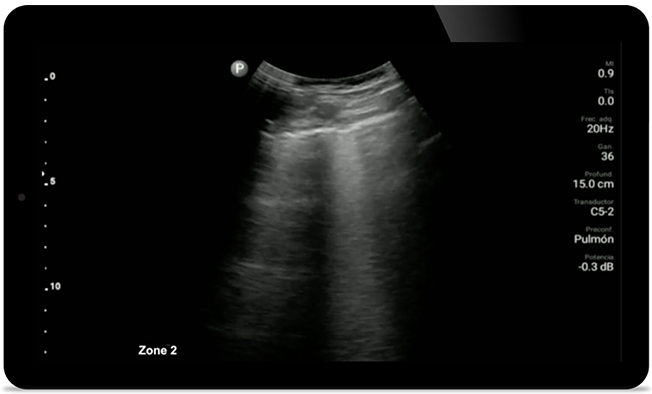

Esté atento a la neumonía por COVID

Lumify puede ayudar a obtener resultados similares a los de una tomografía computarizada de tórax al evaluar la neumonía y el síndrome de dificultad respiratoria en adultos.